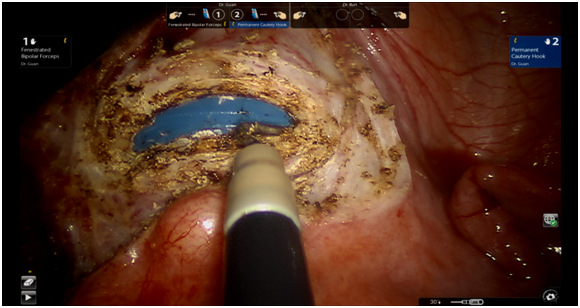

The patient underwent Da Vinci single incision laparoscopic hysterectomy (robotic-assisted total hysterectomy) with bilateral salpingectomy. The hysterectomy was modified by performing colpotomy prior to uterine artery cauterization and cardinal ligament transection (Figure 1) (Figure 2).

Figure 2 Intraoperative picture showing colpotomy done prior to uterine artery ligation.